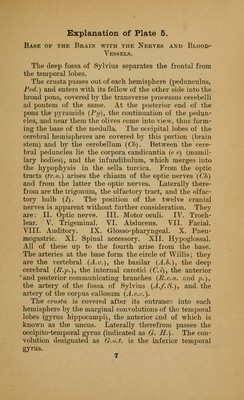

An atlas of the normal and pathological nervous systems : together with a sketch of the anatomy, pathology, and therapy of the same / Tr. and ed. (authorized) by Joseph Collins.

Credit: An atlas of the normal and pathological nervous systems : together with a sketch of the anatomy, pathology, and therapy of the same / Tr. and ed. (authorized) by Joseph Collins. Source: Wellcome Collection.